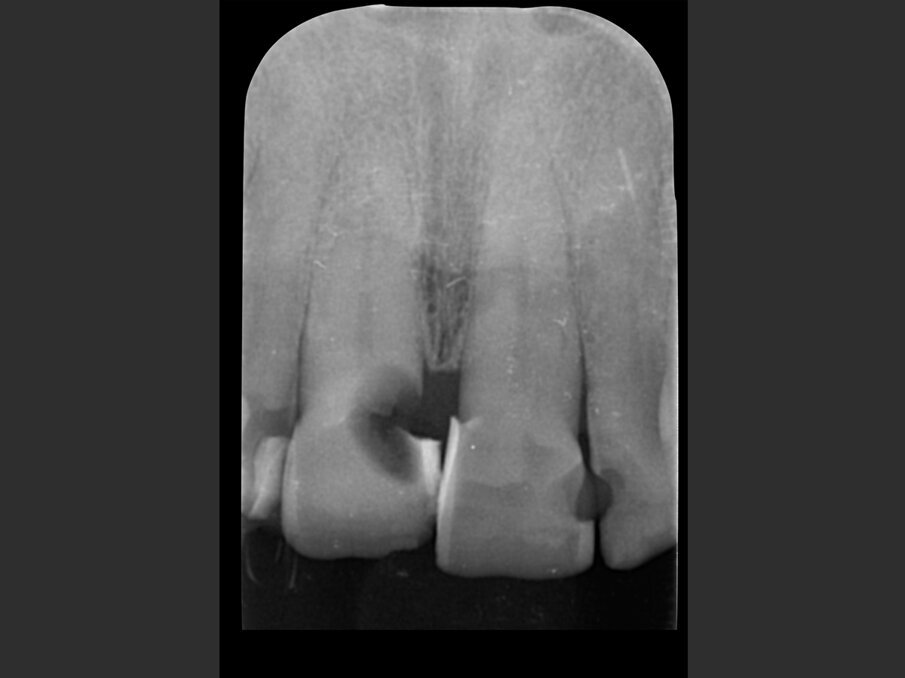

La paziente, donna di 60 anni, non fumatrice ed in buone condizioni di salute generale, si presenta in studio con sintomi di pulpite irreversibile a carico dell’elemento 1.1. L’esame clinico (Figg. 1a, 1b) e radiografico (Fig. 2a) confermano la presenza di una lesione cariosa radicolare che ha colpito il versante mesiale.

Data la profondità della lesione, le opzioni terapeutiche che consentono il mantenimento dell’elemento devono prevedere necessariamente il ripristino dell’ampiezza biologica tramite chirurgia ossea resettiva o trazionamento rapido dell’elemento. La prima ipotesi viene scartata per l’inevitabile slivellamento delle parabole e perdita delle papille interdentali che ne sarebbero derivate; la seconda per il rifiuto della paziente di sottoporsi al trattamento ortodontico, pur se per un periodo di tempo limitato. Si procede quindi con un’indagine radiografica tridimensionale con tecnica Cone Beam (MYRAY Hyperion X9 Pro), per valutare la possibilità di sostituire l’elemento con una corona a supporto implantare. I tagli in sezione sagittale (Fig. 2b) mostrano la presenza di una corticale ossea vestibolare integra e la presenza di una quantità di osso apico-palatale sufficiente per poter ottenere una buona stabilità implantare (classe I secondo la classificazione di Cardaropoli9).

Fig. 2a - Valutazione radiografica iniziale: radiografia intraorale.

Fig. 2b - CBCT iniziale con MyRay Hyperion X9 Pro.